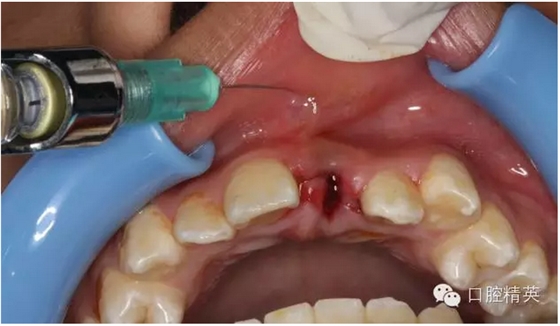

圖12.局部浸潤(rùn)麻醉